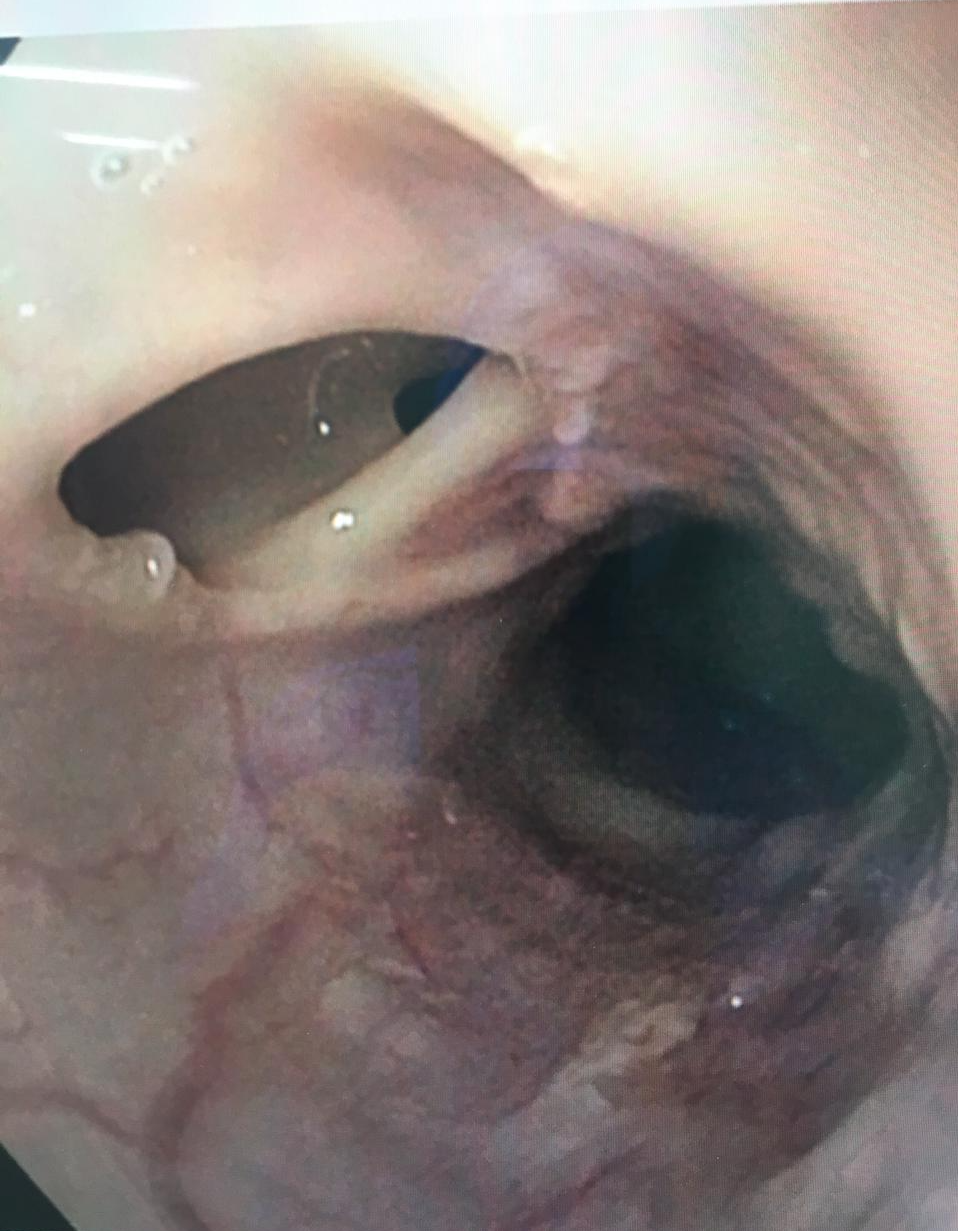

As FTE ou FBE em pacientes com aids são eventos raros e têm com agentes etiológicos M. tuberculosis, M. avium-intracellulare, Candida, Nocardia, CMV e herpes simples. Suas consequências são aspiração contínua, sépsis e insuficiência respiratória. Embora possa ocorrer em paciente com boas condições de imunidade, na maioria dos casos acomete pacientes com doença avançada, sinalizando mau prognóstico. Nessas condições, as opções de tratamento são paliativas e envolve a colocação de próteses traqueal, brônquica ou esofágica, com potenciais complicações como a formação de tampão de muco, tecido de granulação, migração e perfuração.1,

Em pacientes com boas condições clínicas, a cirurgia pode ser uma opção, com fechamento orificial esofágico primário e possível ressecção de segmento traqueal de acordo com o comprometimento. Em grandes orifícios, pode ser usado uma matriz regenerativa (alloderm) e, em casos extremos, esofagectomia. Complicações são evitadas com elevação da cabeça do paciente no leito, drenagem contínua das secreções, drenagem gástrica por ostomia e inserção de tubo de jejunostomia.3,4